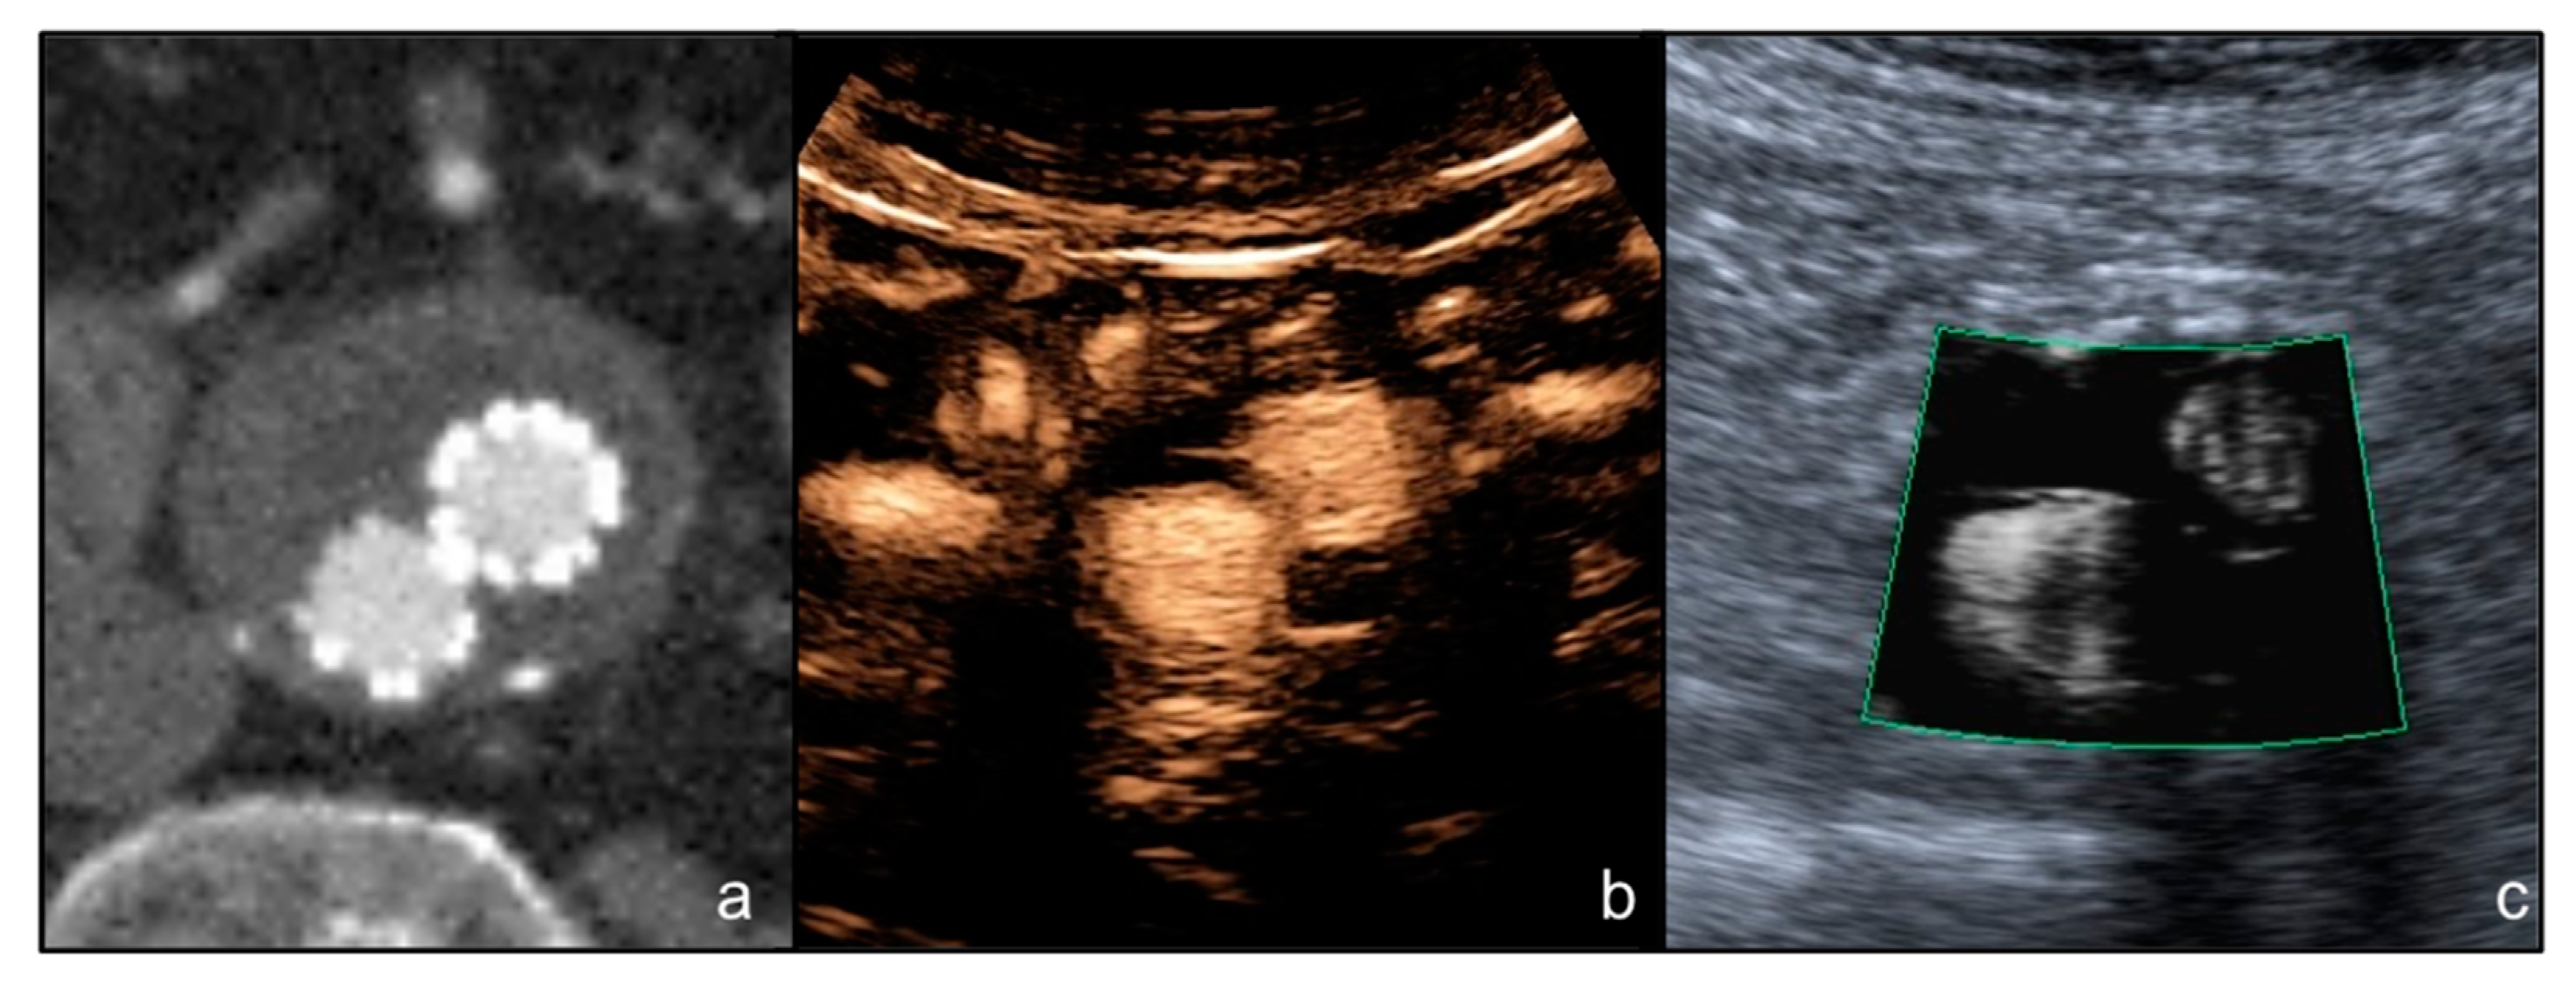

- Cantisani, V.; David, E.; Ferrari, D.; Fanelli, F.; Di Marzo, L.; Catalano, C.; Benedetto, F.; Spinelli, D.; Katsargyris, A.; Blandino, A.; et al. Color Doppler Ultrasound with Superb Microvascular Imaging Compared to Contrast-Enhanced Ultrasound and Computed Tomography Angiography to Identify and Classify Endoleaks in Patients Undergoing EVAR. Ann. Vasc. Surg. 2017, 40, 136–145. [Google Scholar] [CrossRef] [Green Version]

- Gabriel, M.; Tomczak, J.; Snoch-Ziółkiewicz, M.; Dzieciuchowicz, Ł.; Strauss, E.; Oszkinis, G. Comparison of Superb Micro-Vascular Ultrasound Imaging (SMI) and Contrast-Enhanced Ultrasound (CEUS) for Detection of Endoleaks After Endovascular Aneurysm Repair (EVAR). Am. J. Case Rep. 2016, 17, 43–46. [Google Scholar] [CrossRef] [PubMed] [Green Version]